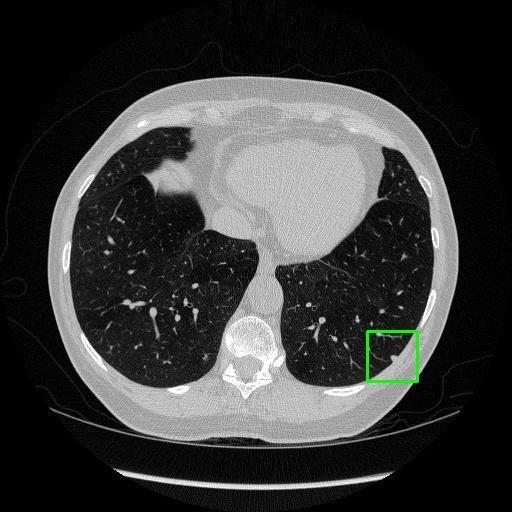

We developed an AI-based system using deep learning models for analyzing lung CT scans to detect and classify pulmonary nodules. We chose the YOLOv11 architecture for its enhanced object detection capability and adapted it specifically for medical imaging, incorporating pixel-level precision and severity classification.

Classification into three severity levels with colored bounding boxes.

Designed a severity classification system that categorizes nodules into null, moderate, and severe using colored bounding boxes, assisting in rapid clinical decision-making.